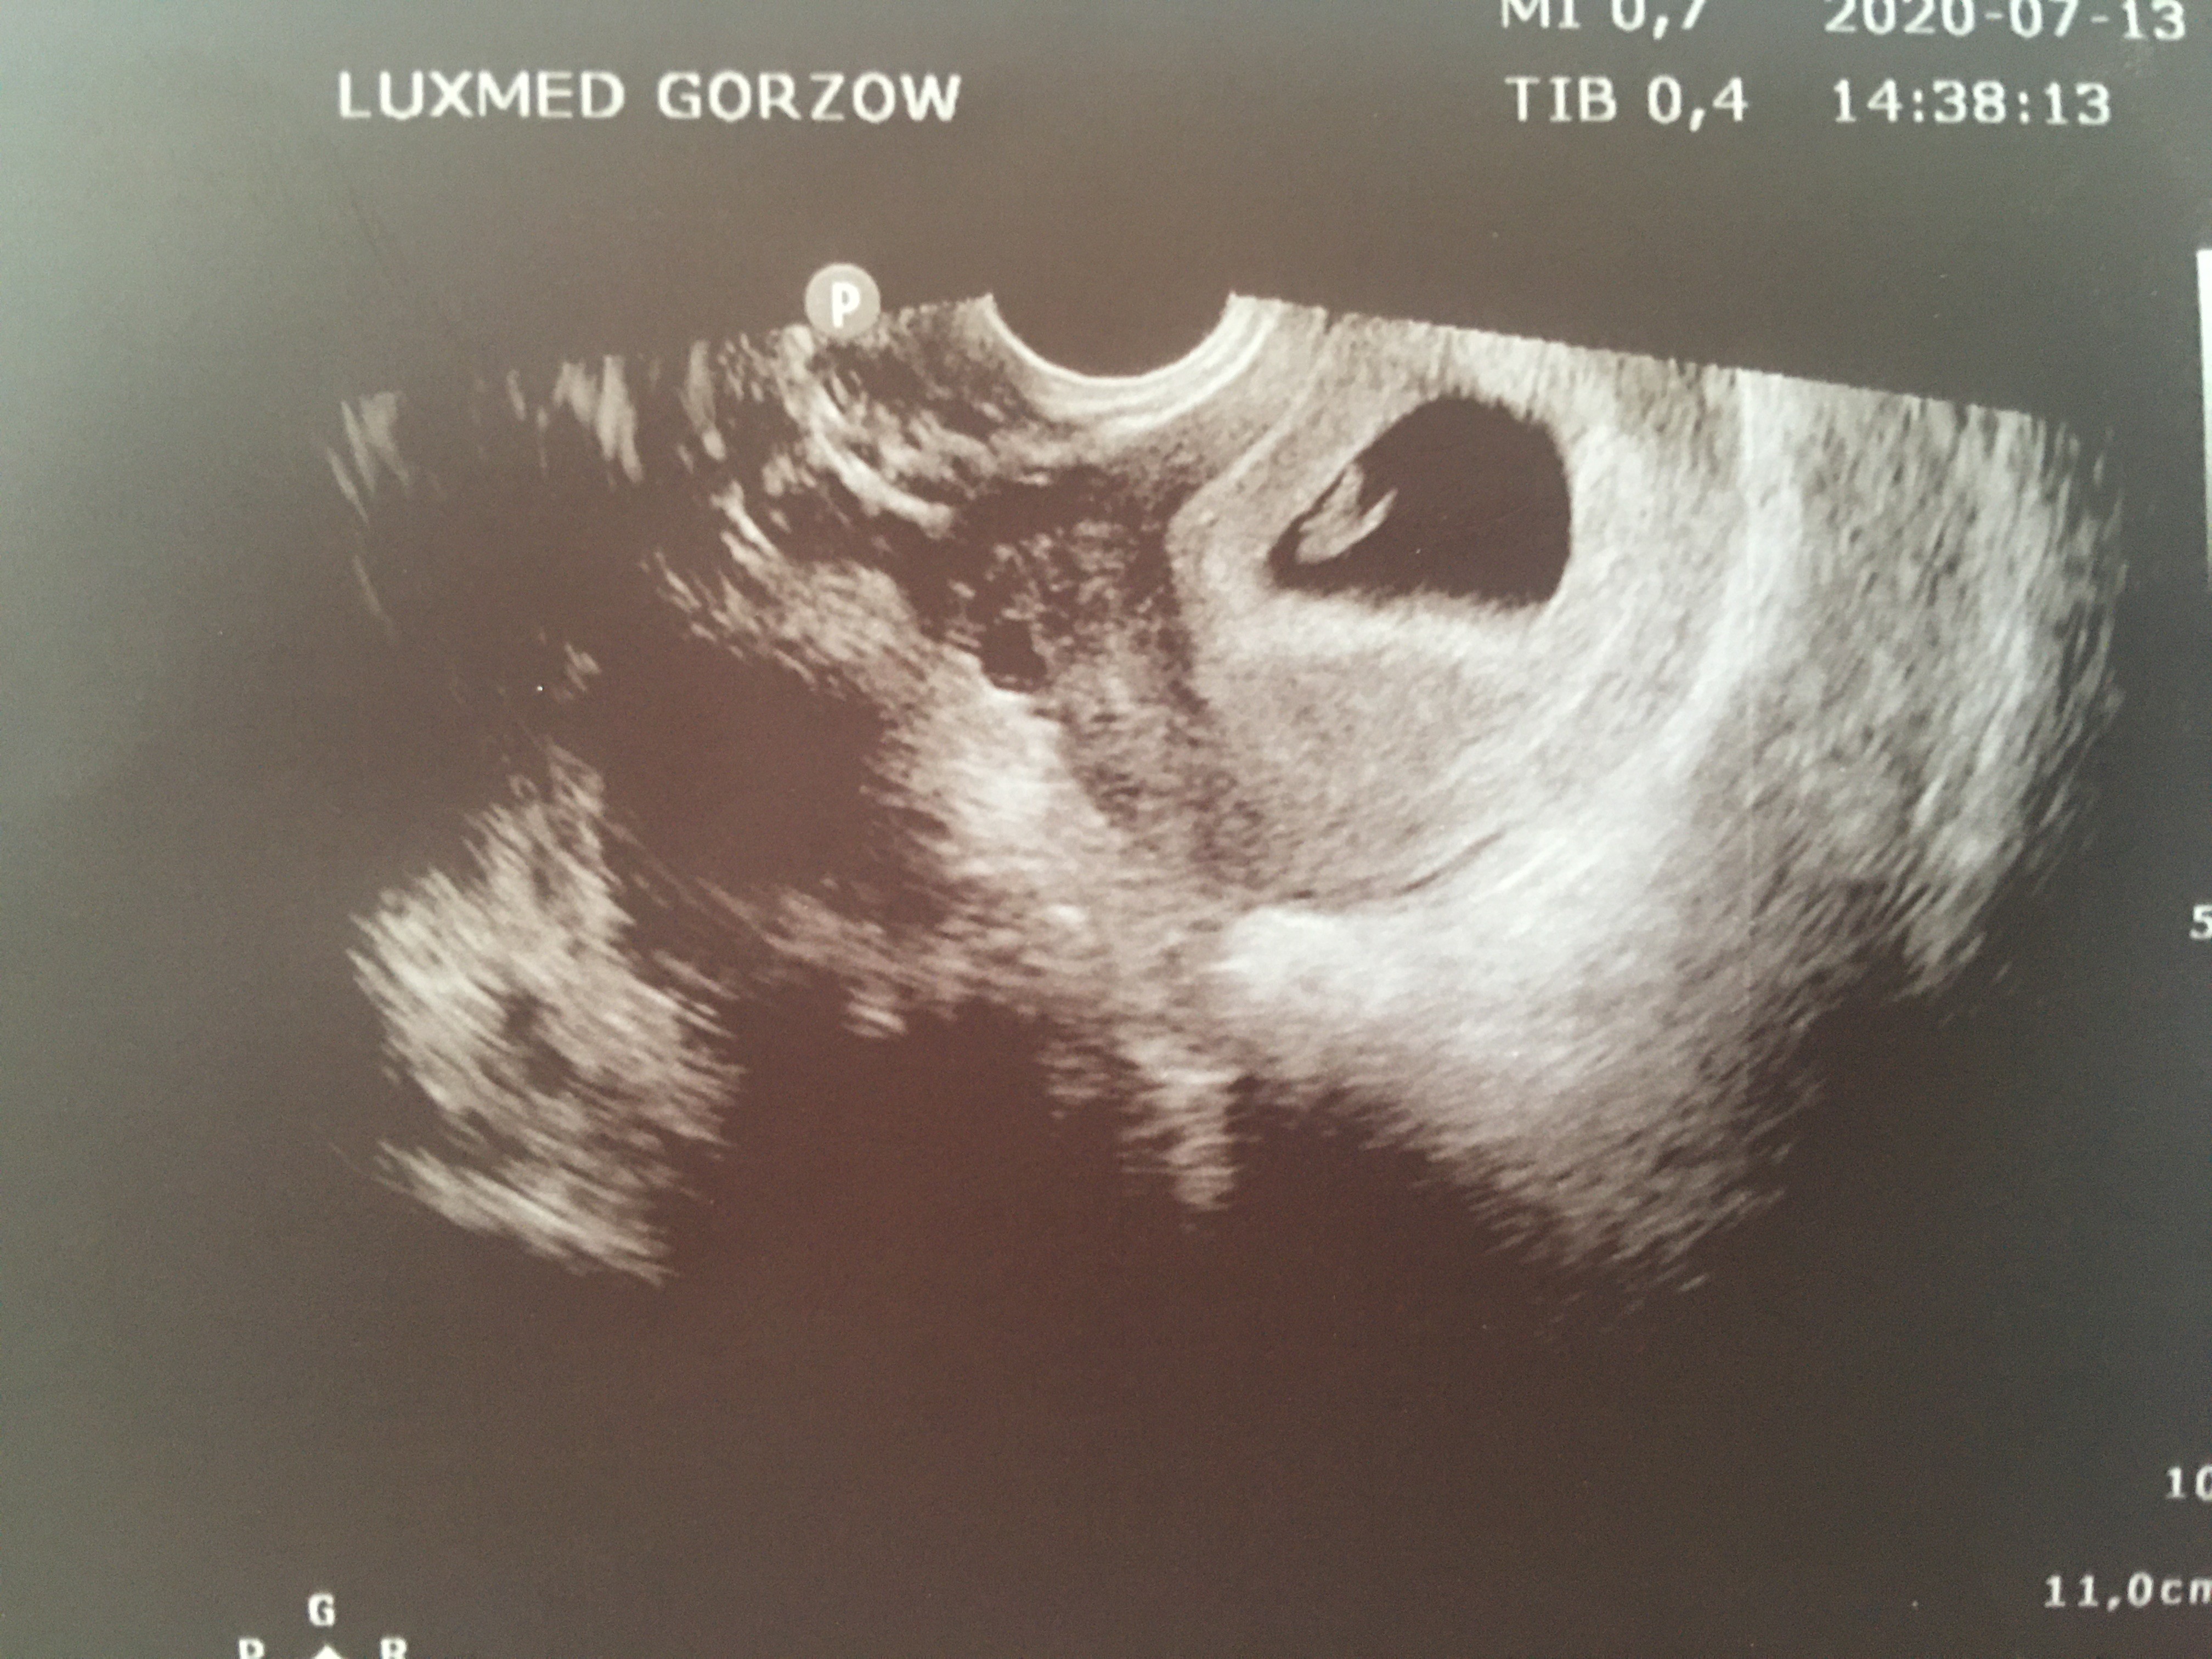

Nowe usg już jest więcej widoczne około 7-8 tydzień. Niestety torbiel nie zmniejsza się dostałam skierowanie do szpitala jutro jadę zobaczymy co zadecydują dalej. Zobacz załącznik 1147878